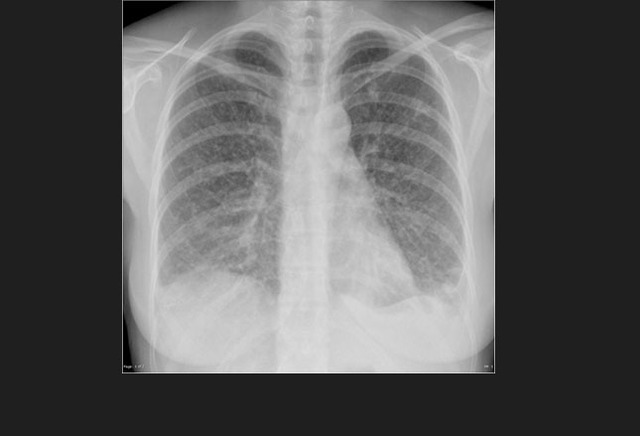

图5. 一位HIV阳性患者的继发性肺结核

HIV改变了结核的发病机制,因此极大的增加了结核进展的风险,导致更容易出现肺外侵犯,出现不典型的X-线表现。

整体而言,结核是HIV血清学阳性患者最常见的机会性感染,也是AIDS患者最常见的死亡原因。